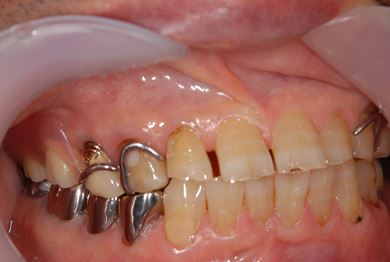

抜歯即日スピードインプラント治療+歯周外科治療

| 性別/年齢 | 男性 / 62歳 | ||||||||||||||||||||||||||||||||

| 主訴 | 左下の奥歯のブリッジがゆれて、痛みがある。 | ||||||||||||||||||||||||||||||||

| 治療方針 | 抜歯と同時にインプラント埋入を行い、治療期間を短縮する。 | ||||||||||||||||||||||||||||||||

| 治療内容 | インプラント2本(抜歯即日スピードインプラント)、ハイブリッドセラミッククラウン2本、歯周外科治療 | ||||||||||||||||||||||||||||||||

| 総治療費 | 771,960円 | ||||||||||||||||||||||||||||||||

| 治療期間 | 6ヶ月 |